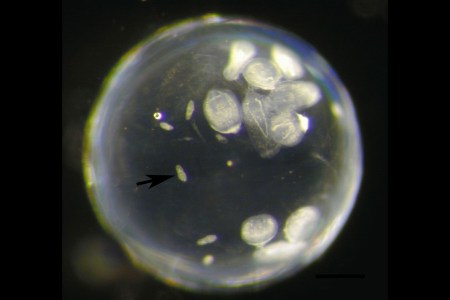

Parasite Can Hijack Its Host’s Brain by Burrowing Into Its Eye

New study shows how eye flukes can control the behavior of their host from within.